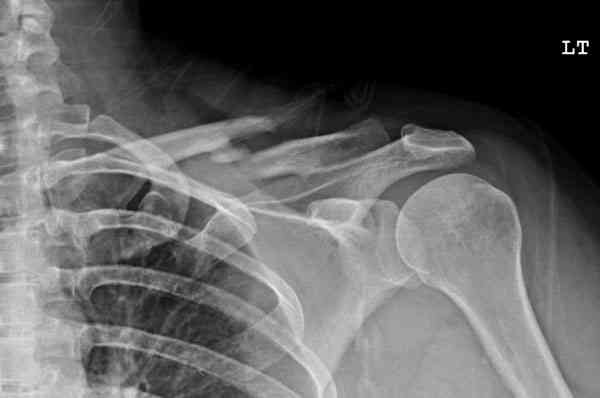

iГГШ> выполнения новокаиновой блокады дежурной бригадой выполнена закрытая

ГГШ> репозиция, наложены кольца Дельбе. Результаты репозиции показаны на

ГГШ> Результат стационарного лечения приведен на рентгенограмме (Xray_3).

Это картинка то есть через неделю после травмы, при выписке? Более чем приемлемо.

Травма амбулаторная, смещение изначально было допустимым, но можно было и подправить, только мы у старших детей применяем шинно-гипсовую повязку. В данном случае репозиция положения не улучшила, на последних рентгенограммах положение отломков удовлетворительное. С уважением, А.В. Шахин

Судя по проекциям ключицы, очевидно разобщение фрагментов, чаще всего сопровождающееся интерпозицией платизмой. для 15 летнего пациента, категории физически активных пациентов выбрал бы оперативный метод( интрамедуллярно

винтом с частичной резьбой).

Для выбора метода лечения перелома ключицы при первичном обращении рутинно необходимо выполнение Рг графии в двух проекциях. принимать решение о

тактике лечения перелома, руководствуясь только одной передне-задней проекцией ошибочно( почему-то в отношении ключицы подобная недооценка

перелома наиболее часто встречается).